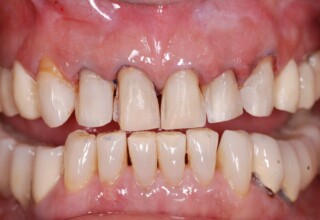

Porcelain Veneers

The best way to solve esthetic problems of the anterior teeth. They combine very little tooth grinding with very high esthetic performance. In the following extensive case anterior teeth presented with: old restorations, staining, poor shape, length and tooth –gingiva ratio. Meticulous diagnostic waxing was performed on study casts and temporary veneers were manufactured. Temporary veneers were used intraorally to evaluate the incorporated changes and to further modify and adjust were needed. When esthetics and function were approved by the patient and were satisfying for the operator the temporaries were used as a guide for the final porcelain veneers. The five final veneers on the upper anterior teeth restored the smile of the patient to almost perfection.

Initial appearance

Final appearance